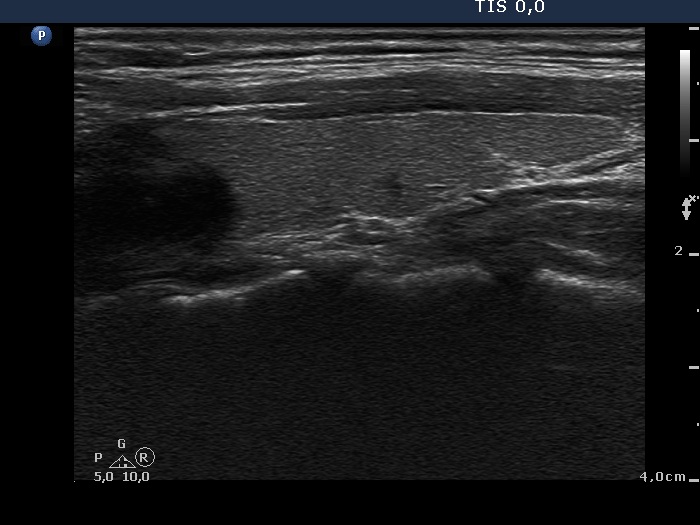

Discrete lesion or nodule in Hashimoto's thyroiditis - case 26 (1048) (ultrasonographic picture 6)

Left lobe, longitudinal scan.